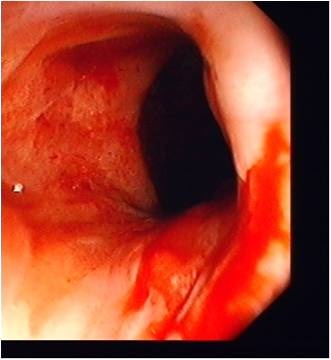

Owrzodzenia, nadżerki, krwawienia czy nawet perforacje jelita to tylko niektóre z nich. Istnieją także prace, które wykazują zależność między stosowaniem NLPZ a rozwojem nieswoistych zapalnych chorób jelit (nzchj). Wykazanie takiej zależności jest niezwykle istotne, jako że etiologia nzchj pozostaje nadal niewyjaśniona. Wspomniane badania mają jednak szereg mankamentów, a głównym z nich jest w większości ich retrospektywny charakter i pewne ryzyko przeszacowania zależności między stosowaniem tych leków, a rozwojem choroby z kręgu nzchj.